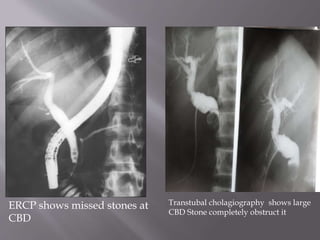

ERCP shows missed stones at

CBD

Transtubal cholagiography shows large

CBD Stone completely obstruct it